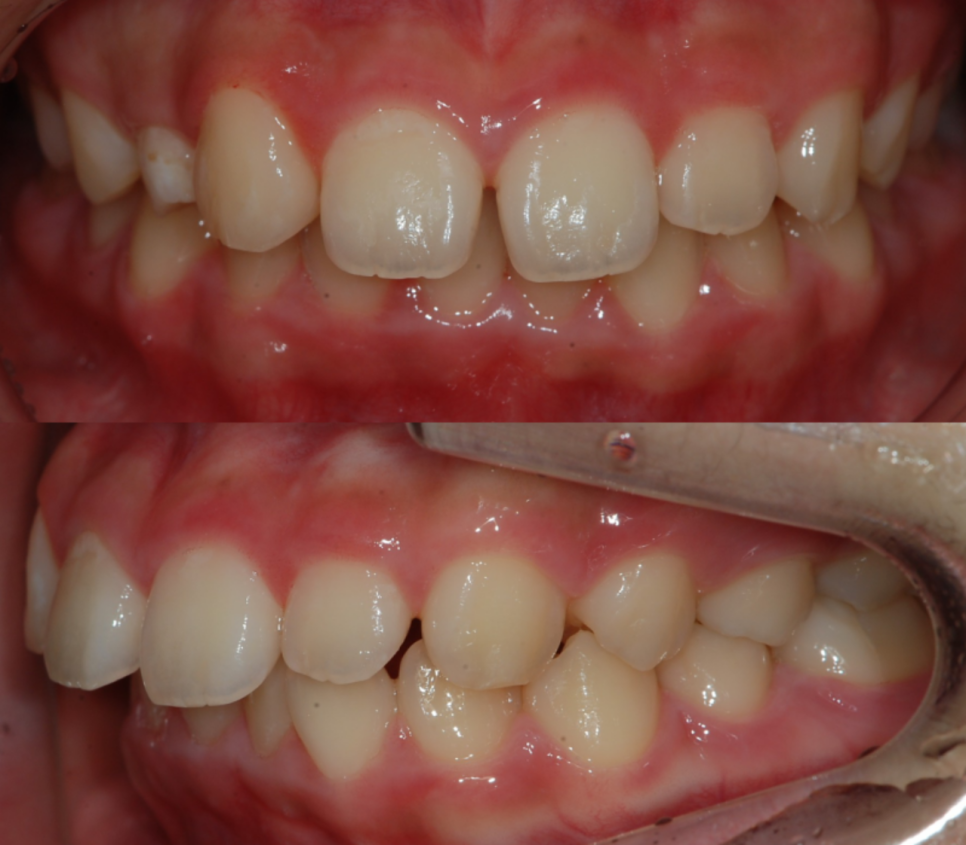

돌출입 교정 전/후

측면에서 볼때 돌출입이 심각한 상태

먼저 교정 진행 전에 촬영한

사례자분의 모습인데요.

위 사례자분께서는 평소

심하게 앞으로 튀어나온 앞니 때문에

외적인 콤플렉스가 매우 심해

맘 편히 웃지 못하고 사진도 잘

찍지 않았다고 하셨는데요.

부정교합으로 인해 치아가 맞물리지 않는 상태

사례자분의 경우 상악의 앞니가

심하게 앞으로 돌출된 형태를 띠고

있었으며 상, 하악의 치아가 거의

맞물리지 않을 정도로 심각한

부정교합이 있는 상태였습니다.